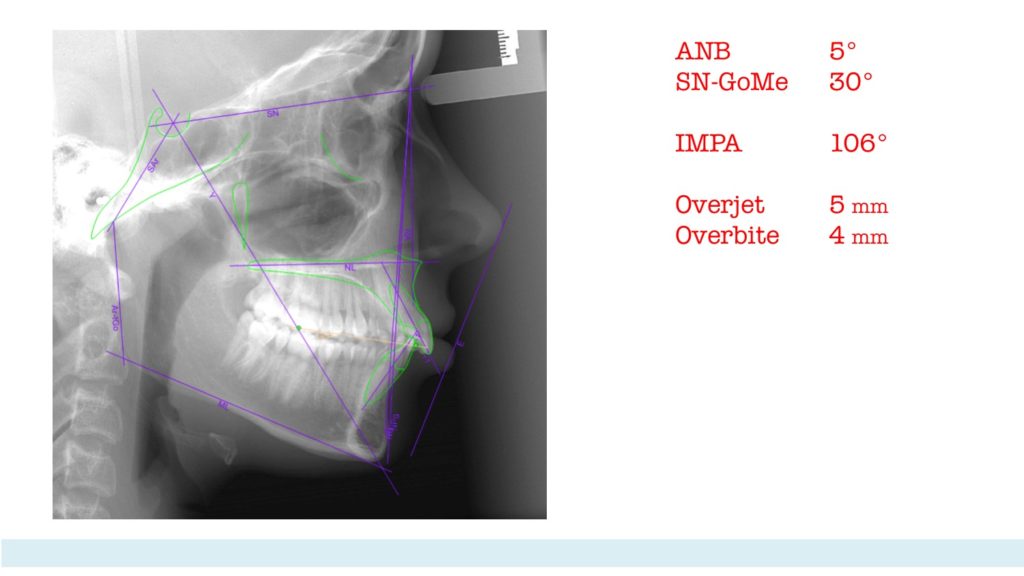

Final lateral x-ray and superimpositions. I was lucky that some residual growth was there during the period of treatment with braces and some CLII elastics. The overbite and overjet were diminished and matched to the planned values.